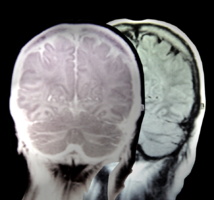

Imagen: Marem. Fuente: PhotoXpress.

Se trata de la herramienta AlzTools 3D Slicer, que utiliza rutinas espaciales para analizar las imágenes de resonancia magnética (IRMs). Ha sido desarrollada por los ingenieros informáticos de la empresa española Elecnor Deimos, basándose en la experiencia acumulada durante los años de desarrollo de software para la misión Envisat de la ESA.

“El análisis de las imágenes por satélite se puede comparar con lo que tienen que hacer los médicos para comprender el resultado de los escáneres cerebrales, como las IRMs”, explica Fernández de la Peña.

“Los médicos también tienen que identificar ciertas características en la imagen que pueden ser un indicativo de disfunciones cerebrales”.

Los científicos de Deimos utilizan AlzTools para analizar los datos tomados por un escáner cerebral, en vez de un satélite de observación de la Tierra. En lugar de una cosecha o de una carretera, analizan zonas del cerebro como el hipocampo, cuya atrofia está relacionada con el Alzheimer. En ambos casos, señala Fernández de la Peña, “Tienes que encontrar sentido a una tonelada de datos”.